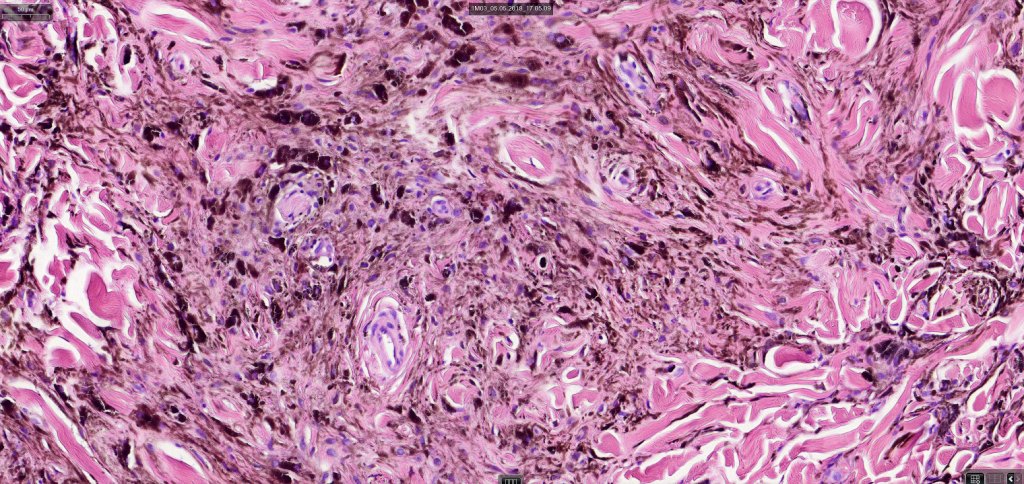

Cellular blue nevus

This uncommon most often devlops on the buttocks, sacrococcygeal region & distal extremities although it may be seen at just about any site. It shows a predilection for females and is diagnosed most often in the 2nd-4th decade. It presents as a blue-black/ or black nodule measuring 1-2 cm in dianeter. Similar to common blue nevus, the cellular variant can be encountered in a wide range of non-cutaneous locations.

Histological features

•Most characteristic is the dumbbell silhouette although a plague morphology may also be encountered

•Combined nevus variant

•Admixture of spindle cells, pigmented bipolar or dendritic cells & melanophages

•Cytoplasm is pale and nuclei are small with inconspicuous nucleoli

•An alveolar pattern is characteristic particularly with clear cell nodules

•Mitoses are typically very sparse or absent

•No atypical mitoses

•No Necrosis or lymphovascular invasion

•Multinucleate giant cells sometimes present

•Stromal fibrosis, myxoid change, vascular hyalinization with cyst formation are often seen

•Some tumors are composed spindle cells in a fascicular or neuronevoid pattern

•Perineural involvement may be seen

•Balloon cell change

•Desmoplastic variant

•Hypopigmented variant